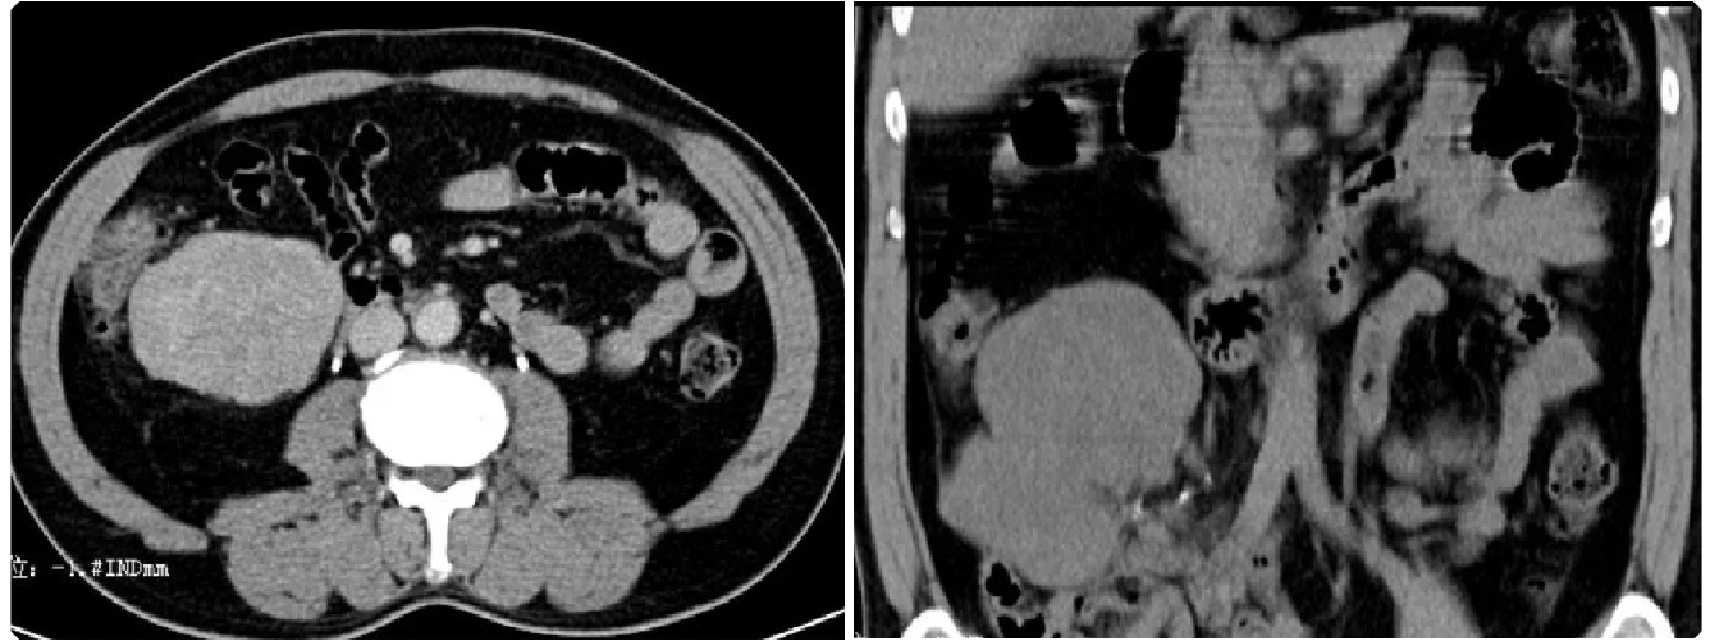

平滑肌肉瘤为腹膜后发病率仅次于脂肪肉瘤的恶性肿瘤,是第二常见的原发性腹膜后肉瘤。主要起源于腹膜后血管壁的平滑肌组织,胚胎残余平滑肌及腹膜后潜在间隙平滑肌等。平滑肌肉瘤多见于40-70岁中老年人,2/3发生于女性,肿瘤生长迅速,70%首要症状为腹胀。

腹膜后平滑肌肉瘤多位于左上腹膜后、盆底。瘤体多较大,形态不规整呈分叶状改变。常与主动脉及下腔静脉分界不清,容易侵犯腹膜后大血管,此征像较有特征。肿瘤单发多见,多发少见,体积一般较大,有包膜(不同参考资料表述有异),形态一般呈椭圆形或分叶状,密度不均匀,实性部分呈明显低密度,囊变、坏死、出血多见,如肿瘤内有出血,低密度区内可出现高密度影,但肿瘤钙化少见。肿瘤血供多丰富,增强扫描呈轻度渐进性强化或中度至明显强化。肿块常与下腔静脉或其它大静脉分界不清。一般没有淋巴结转移,血行肝转移最多见。

917bfe88330e9a51bacfc381b0a24818.png 病例 6:腹膜后平滑肌肉瘤2例

(① 血管内外;② 血管腔外)① 腹膜后肿块可见侵犯右肾血管、下腔静脉,密度不均匀,有囊变坏死,增强后边缘性延迟环状强化。② 腹膜后肿块与右肾血管,下腔静脉及腹主动脉分界不清,肿块密度不均匀,内可见囊变坏死区及高密度灶(平滑肌肉瘤瘤内如有出血,低密度区内可见高密度出血影,但通常不钙化),增强扫描呈明显不均匀强化,囊变区未见强化。